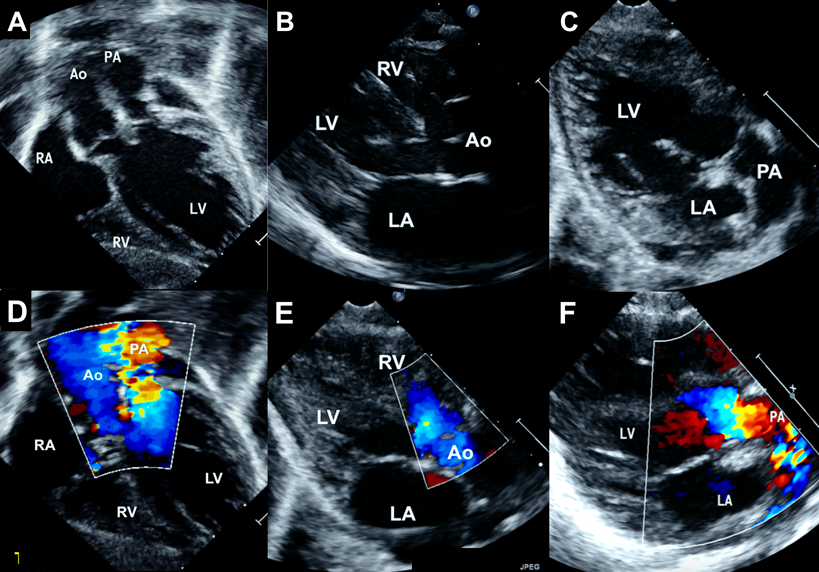

Fig. 2 Echocardiogram of first patient–continued (Movie 2)

Subxiphoid shortaxis view (A) showing aortic origin from the left ventricle with color doppler flows (B) as well as pulmonary artery origin from the left ventricle (D) with color doppler flows (E). Parasternal short axis view (C) shows normal great artery relation at the level of aortic root, with a single coronary artery from the anterior facing sinus. A short axis view at a higher plane (F) again reconfirms normal great artery relation. Ao, aorta; LA, left atrium; LCA, left coronary artery; LV, left ventricle; PA, pulmonary artery RCA, right coronary artery; RV, right ventricle.